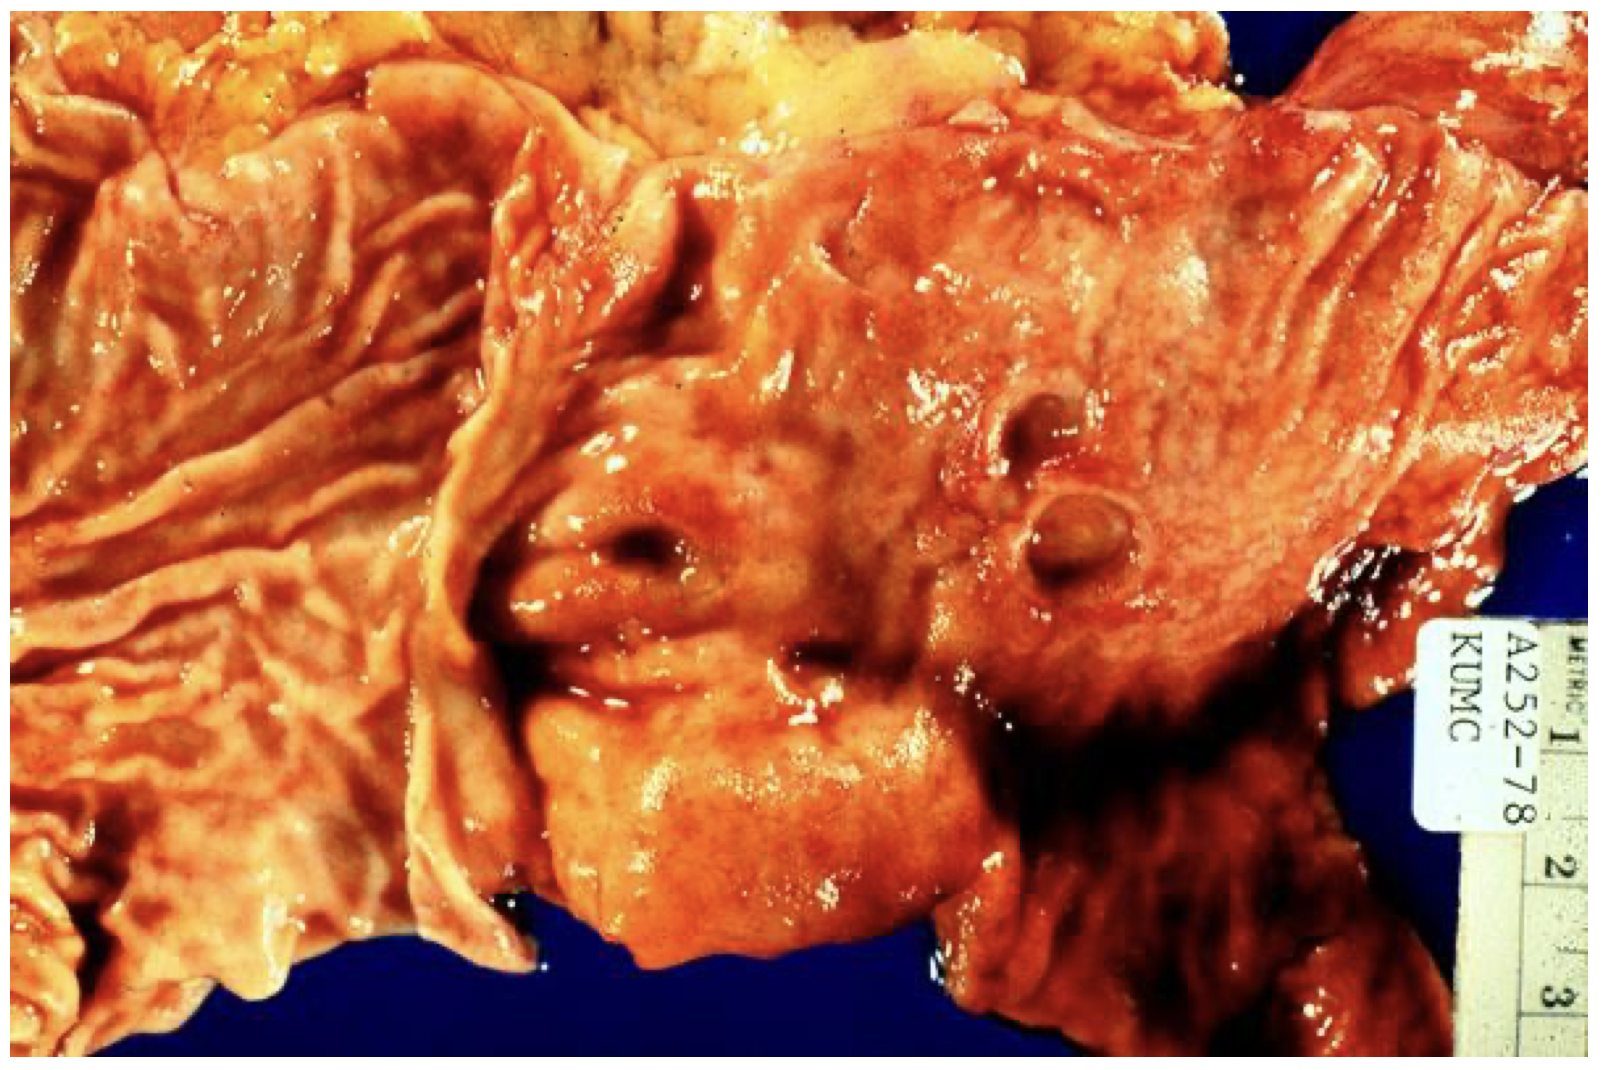

Duodenum, multiple peptic ulcers, gross

This gross photo was taken at the pylorus, with the stomach on the left and the duodenum on the right. Several ulcers are seen. If these become severe, they can perforate the bowel, and air could be seen under the diaphrams on an upright chest x-ray. This is a surgical emergency. The ulcers could also erode into the pancreas. The latest thinking is that ulcers may be infectious, caused by an organism called Helicobacter pylori.